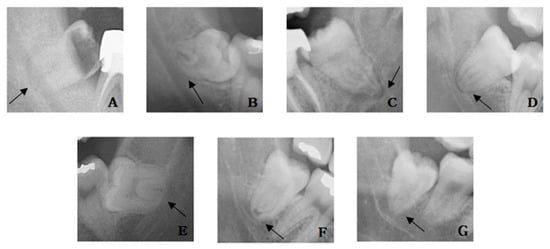

2.2. Panoramic Radiograph

The relationship between the IAN and the mandibular third molar root was observed on panoramic radiography. Based on seven radiographic signs suggested by Rood and Shehab [20], darkening and bifid of the root apex at the IAN area was included as the case of darkening of the root because it was not easy to distinguish. In addition, there were cases where the dark line is visible at the root apex, and this case was also investigated. The radiographic signs were divided into a total of seven observations (Figure 3 and Figure 4): (1) cases where the root was darkened in the IAN area, (2) cases where the root was curved at the IAN area, (3) cases where the root was narrowed in the IAN area, (4) cases with a dark line at the root apex, (5) cases with the loss of the white line of the IAN at the root area, (6) cases with a narrowed IAN at the root area, and (7) cases with a change in the pathway of the IAN at the root area.

Figure 3. Rood and Shehab classification of radiographic signs: (A) root darkening, (B) root deflection, (C) root narrowing, (D) dark line in apex, (E) loss of white line, (F) inferior alveolar nerve (IAN) narrowing, and (G) IAN diversion.

Figure 4. Panoramic view. Arrows indicated the panoramic signs: (A) root darkening, (B) root deflection, (C) root narrowing, (D) dark line in apex, (E) loss of white line, (F) inferior alveolar nerve (IAN) narrowing, and (G) IAN diversion.